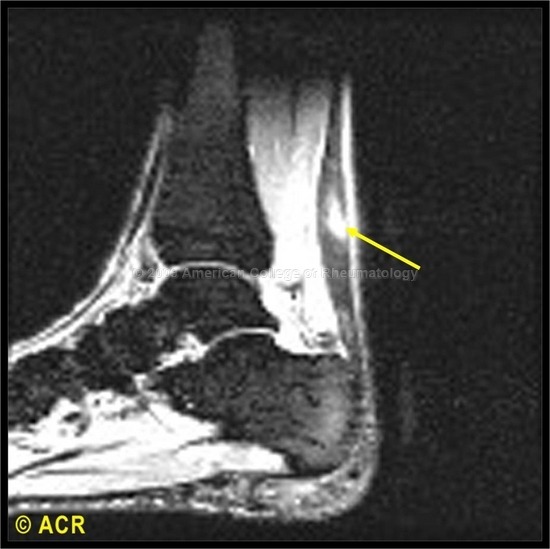

족근동 증후군(Sinus tarsi syndrome)은 족근동 내부에 정상적인 지방 조직의 감소가 나타난다. 급성 또는 아급성기에는 염증으로 낮은 T1 신호와 높은 T2 신호가 나타난다. 만성의 경우에는 섬유증으로 낮은 T1과 T2 신호를 보인다. 환자는 발목의 위약감과 불안정성을 호소하는데, 족근동 위의 촉친할 수 있는 압통이 나타난다. 대부분의 경우는 특발성이지만, 몇몇의 환자는 발목의 내전 손상의 병력을 가진다. 족근동 증후군의 다른 경우들은 류마티스 관절염이나 통풍, 결절종(ganglion cyst)과 같은 염증 상황에서 나타난다.

△ 시상면 T1 강조 영상은 좌측의 족근동에서의 정상적인 지방 소멸로 인해 저강도로 나타남을 보여준다. 우측은 정상적인 영상

△ 시상면 T2 강조 영상에서는 고강도의 신호로 나타난다.